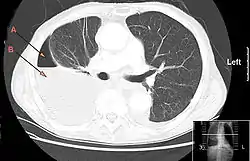

![]() صورة مقطعية للصدر يظهر فيها استرواح الصدر الموهي من الدبيلة الجنبية. السهم (A) يشير إلى هواء والسهم (B) يشير إلى سائل صورة مقطعية للصدر يظهر فيها استرواح الصدر الموهي من الدبيلة الجنبية. السهم (A) يشير إلى هواء والسهم (B) يشير إلى سائل | |